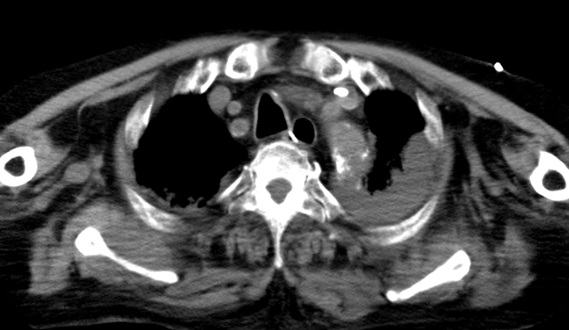

- 9月12日:血胸・緊張性血胸の痕跡

X線・CTで縦隔拡大や胸水の所見あり。輸血が必要になるほどの貧血は心タンポナーデのみでは説明不能。

証拠:胸腹部CT・血胸

状態が悪化した9月12日に頭部・胸腹部CTが撮影された。医師説明およびカルテ記載には、そのCTの目的として 「貧血が進行したため出血源精査目的」とあるが、頭部への出血で貧血が進行することは通常考えられず、 出血源精査目的であれば、胸腹部CTで十分のはずである。 このCTの目的は、医学的には死後AI(Autopsy Imaging)に他ならない。 つまり、死因の特定である。

この時、同時に撮影された胸腹部CTでは、大動脈周囲に三日月状の血種様の病変が認められ、両胸腔にはフィブリン化したと思われる血餅の残存病変が多数認められた。大動脈損傷に伴い大動脈から胸腔に出血していた証拠であり、当初のPCI(カテーテル治療)での医療事故の痕跡がこのCT画像に残っている。